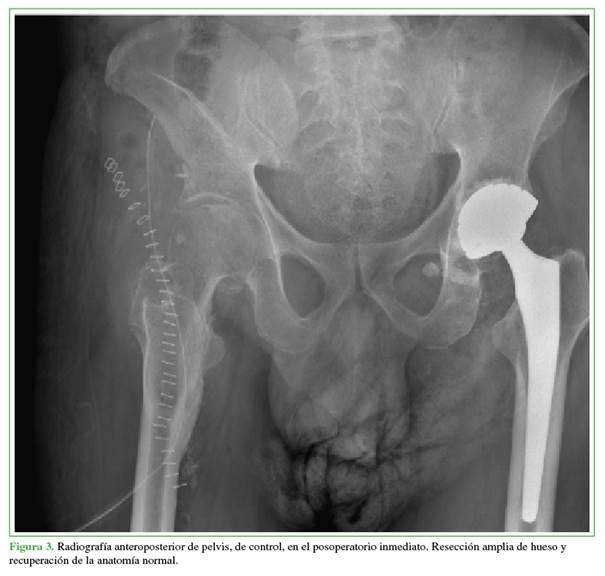

En el seguimiento radiográfico inmediato y a los tres meses de la cirugía (Figuras 3 y 4), se confirmó la resección completa de la osificación. Clínicamente, al año de la cirugía, el paciente tenía una notable mejora en los arcos de movilidad, con extensión completa y flexión de 110°. Además, logró retomar la marcha con la ayuda de un caminador. Continúa con terapia física y fortalecimiento del cuádriceps bajo la supervisión de Fisiatría, sin dolor ni complicaciones adicionales hasta la fecha.